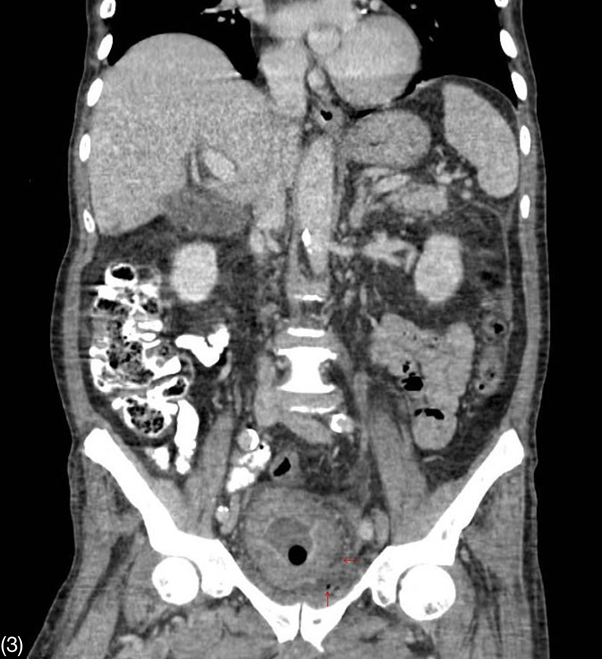

Figure 3 Contrast-enhanced CT scan of the abdomen in coronal view.

Thickening of bladder walls and emphysema in the prevesical space.